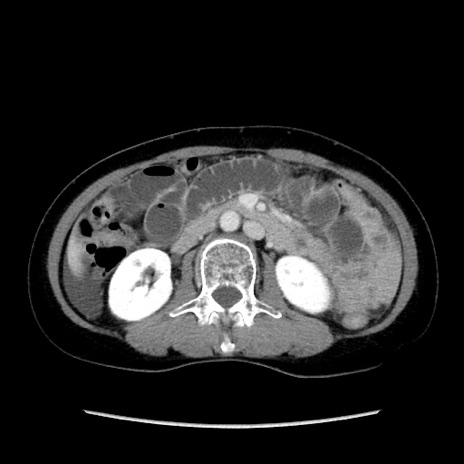

症例32(横断像)

【症例】40歳代 女性

【主訴】上腹部痛、嘔気・嘔吐

【現病歴】約9時間前頃から急に上腹部痛、嘔気、嘔吐が出現。改善しないため救急要請。

【既往歴】子宮頚癌(広汎子宮全摘術、放射線療法)、腸閉塞

【身体所見】腹部:平坦、軟、腸雑音亢進、上腹部を中心に腹部全体に圧痛あり。

【データ】WBC 8400、CRP 0.03